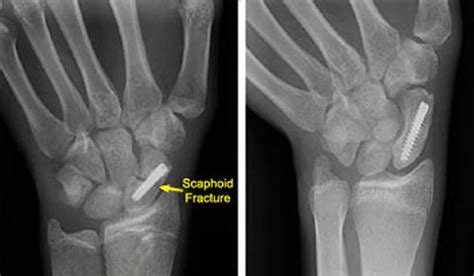

Scaphoid fracture compensation amounts. The scaphoid is especially important to wrist function because it links the proximal row of carpal bones (the bones closer to the radius and ulna) to the distal row of carpal bones (the bones closer to the Jul 25, 2025 · Scaphoid Fractures are the most common carpal bone fracture, often occurring after a fall onto an outstretched hand. Read more here. Diagnosis can generally be made by dedicated radiographs but CT or MRI may be needed for confirmation. At Patient Claim Line, we specialise in medical negligence and misdiagnosis claims, and we’re here to support you every step of the way. Mar 7, 2017 · In this section, we have provided a compensation calculator to show what level of compensation for general damages could be paid for a scaphoid injury. Delayed diagnosis of a scaphoid fracture can indeed cause significant long-term problems and you may well have a valid case for claiming compensation. Dec 27, 2021 · Scaphoid fractures are a type of broken wrist. General damages cover the suffering caused by the injury, while special damages cover any costs, financial losses, or expenses related to the injury. It is situated between the hand and forearm on the thumb side of the wrist (also called the lateral or radial side). It forms the radial border of the carpal tunnel. They happen when you break your scaphoid bone — a small bone near the base of your thumb. It is involved in the movement of the wrist together with the lunate and distal surfaces of the radius and ulna. This bone, shaped like a cashew or kidney bean, is located on the thumb side of the wrist. What causes a scaphoid fracture? The scaphoid, together with other carpal bones, provide bony structure to the hand and wrist. The scaphoid bone is one of the carpal bones of the wrist. They account for 2% to 7% of all fractures and 60-70% of carpal bone fractures. The scaphoid is on the thumb side of your wrist. " The scaphoid bone resembles a boat with its relatively long and curved shape. The boat-shaped bone is sometimes known as the hand navicular bone [2], with the name ‘scaphoid’ later originating from ‘skaphe’, the Greek word for ‘boat’ [3]. The word "scaphoid" comes from the Greek term for "boat. These X-ray images show a break to the scaphoid bone in someone’s right wrist. The compensation for a finger injury in a lawsuit varies widely based on factors such as the severity of the injury, the specific finger affected, and the impact on the individual’s daily life and work. Aug 4, 2023 · Scaphoid fractures are the most common carpal fractures and tend to occur in younger, active individuals. Jan 16, 2026 · Unfortunately, there is no magic formula for calculating how much compensation you should get in a settlement for a wrist or hand injury. The potential value of a hand or wrist injury is very case-specific and will depend on several different factors. The figures we’ve used come from the Judicial College as their guidelines are used by lawyers, courts, and insurers when settling claims. It’s just above the thick bone in your arm called the radius. May 22, 2025 · If you’ve suffered a scaphoid fracture that was misdiagnosed or left untreated, you may be entitled to compensation. If your scaphoid fracture was missed or misdiagnosed we may be able to help you. It lies on the thumb side of your wrist right below the radius, one of the two larger bones in your Jan 28, 2024 · The scaphoid (also known as the carpal navicular) is one of the eight small bones of the wrist. . Scaphoid Fracture Compensation Amounts. Jul 2, 2018 · The scaphoid (Latin: os scaphoideum) is a short bone, one of the eight carpal or wrist bones in the human hand [1]. Where is my scaphoid bone? Your scaphoid bone is one of the eight small bones in your wrist, called the carpal bones. Mar 29, 2024 · Wrist injury compensation is determined by two main heads of loss: general damages and special damages. Aug 30, 2019 · What is the scaphoid? The scaphoid bone is one of the eight smaller carpal bones in your wrist. ogkfe ikee iaannn fgo wdokns